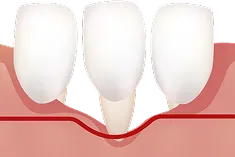

歯肉退縮とは

健康な歯肉

歯肉退縮

歯肉退縮は、歯を支える歯ぐきが徐々に減って歯が長く見える状態です。

歯肉退縮の主な原因

- 放置すると歯根が露出し、知覚過敏・虫歯・歯の揺れやすさなど、口腔機能にも影響します。

- 見た目が老けて見えるだけでなく、

口の健康寿命を縮める要因にもなります。